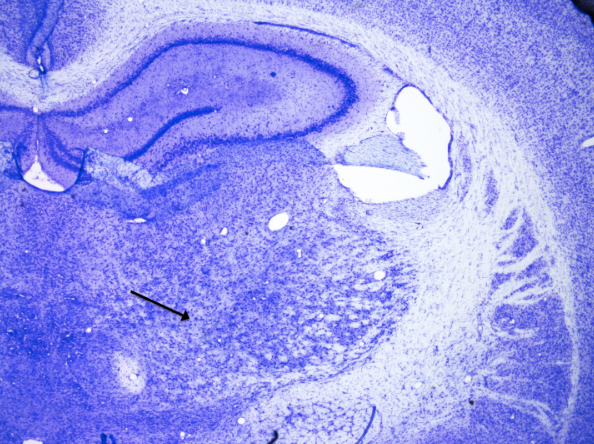

3

New cards

Piriform cortex

knowt flashcard image